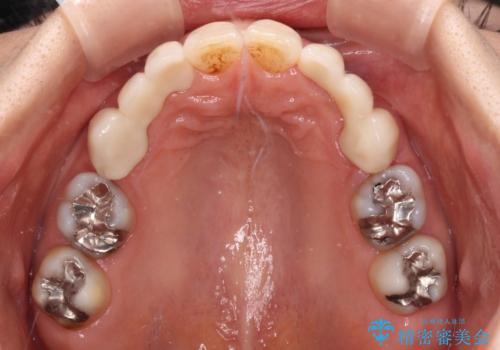

上顎は左右ともに小臼歯が欠損しており、右側は乳前歯が残っている状態でした。

ブリッジによる補綴治療にて、欠損や隙間を補完することとしましたが、神経を取り除いたり、審美的に不自然になることを避けるため、部分矯正を併用することとしました。

乳歯は事前に抜歯することとしました。

隙間が全て閉じたことで、長年食事の度に挟まる不快感が改善されました。

また、正面から見た印象がまるで自分の歯であるような自然な仕上がりとなりました。